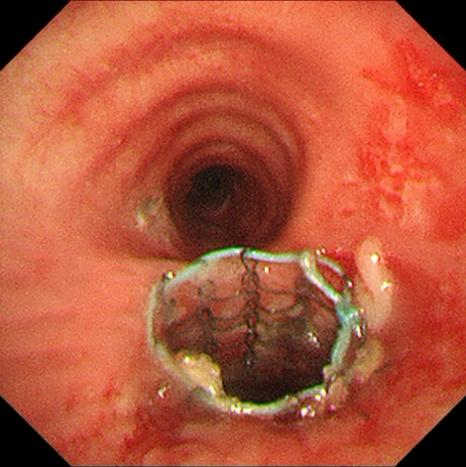

隨后賀龍君副主任在“打通”的右主支氣管繼續(xù)進(jìn)行了氣管支架置入術(shù),以防止氣道短期內(nèi)再堵塞的可能,可謂是“心中有磐石、手中有乾坤”,把“工匠精神”發(fā)揮到了極致!

腫瘤激光消融后氣管支架置入